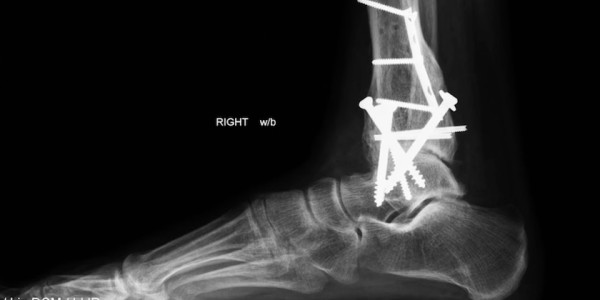

“The X-ray films are good, but even though they’re high quality, they’re two-dimensional,” James Holman, a Tacoma-based attorney, said during a recent interview. “So, what could have been contested by radiology experts in court can’t be contested now, because we have the actual foot and the screw sticking in it.”

Hundreds of documents detailing the VA’s treatment of Kuncl exist in his medical file. But the key records — X-rays depicting his hardware-riddled ankle — might have remained open to dispute by defense experts, Holman said.

The exam confirmed Kuncl’s suspicions: that the VA’s surgeons inserted an orthopedic screw into his ankle that further damaged and exacerbated his injuries.

“My opinion, given with a reasonable degree of medical certainty, is that Mr. Kuncl’s tibial nerve was damaged by the scar tissue associated with an orthopedic screw tip protruding from a bone in his ankle,” Dr. J. Matthew Lacy wrote in his post-examination report.